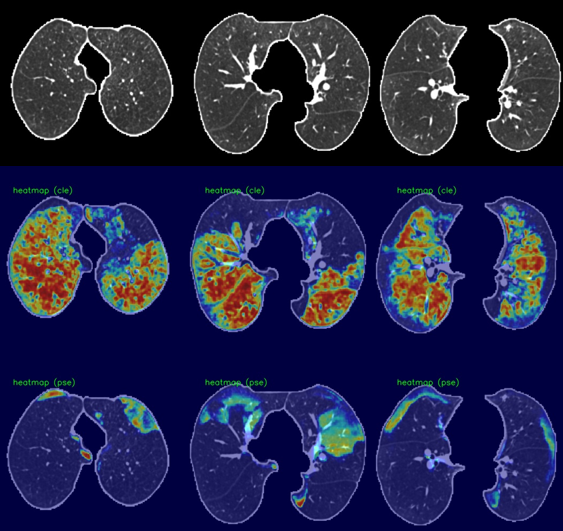

Case I: Confluence in centrilobular, Absent in Paraseptal Emphysema.

Refer to caption

(a) Class Activation Maps. Predicted Advanced for centrilobular, Substantial for Paraseptal.

(b) Regression Activation Maps. Predicted Advanced for centrilobular, Mild for Paraseptal.

Case II: Advanced in centrilobular, Substantial in Paraseptal Emphysema.

(a) Class Activation Maps. Predicted Advanced for centrilobular, Absent for Paraseptal.

Figure 3: Dense class activation maps (left) versus dense regression activation maps (right), We show two cases, and each consists of three rows. The first row shows the input image (cropped and masked by the lung segmentation), the second row illustrates the activation maps for the centrilobular emphysema, and the third row shows the activation maps for the paraseptal emphysema.

We utilized dense activation maps to visualize the features that correspond to the classification decisions. As shown in Figure 3, we present the dense class and regression activation maps on two examples of predicting centrilobular and paraseptal emphysema subtypes. Each example consists of two images, with 3×3333\times 3 tiles, where the left image displays the dense class activation maps and the right image displays the dense regression activation maps. The three columns in each image are sampled axial slices from the input CT scan. For each image, the rows represent the preprocessed input CT scan, the activation map for centrilobular emphysema, and the activation map corresponding to paraseptal emphysema.

In general, the dense class activation maps do not necessarily align with object contours, e.g., blobs of paraseptal emphysema in the second case (Fig. 3 Case II (a)). Naturally, class activation maps only reflect discriminative regions responsible for classification. By utilizing the reconstruction network to generate dense features, our network’s dense class activation maps already provide improved localization compared to the class activation maps generated by the Fleischer algorithm (which tend to be blurry blobs, as seen in their publication). The application of regression training further improves lesion localization, as can be seen in the subpleural paraseptal emphysema in the second case (Figure 3, Case II(b)) and small blobs following the secondary lobular structures in the first case (Figure 3, Case I(b)). Additionally, due to the use of the overlapping loss (Eq.2), the centrilobular and paraseptal activations do not overlap in the dense regression activation maps (Figure3, Case II(b)), unlike in the class activation maps. For instance, in the first case, both class activation maps responded to the same regions in the right lobe (Figure 3, Case I(a)). This highlights the effectiveness of our proposed method in providing improved lesion localization compared to the Fleischer algorithm.